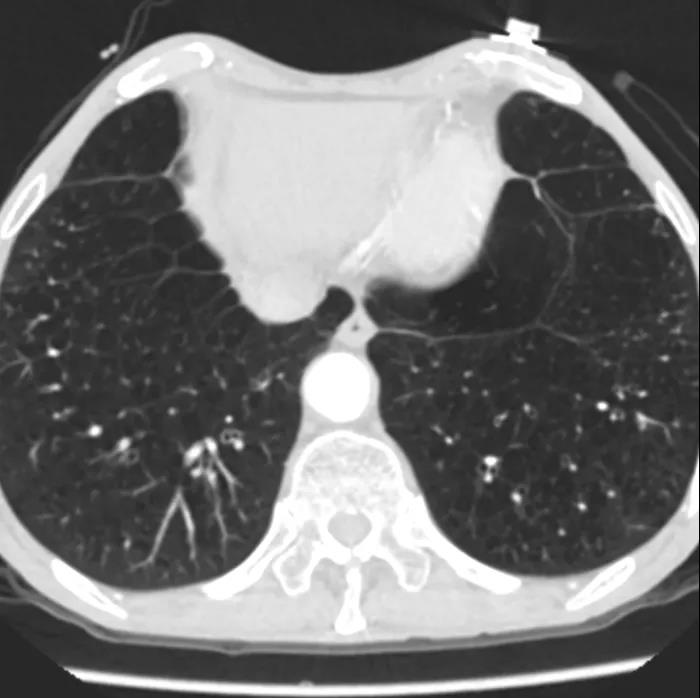

患者男性,67岁,活动后胸闷气促4年余。术前心脏超声提示先天性二叶式主动脉瓣畸形伴极重度狭窄及轻度反流,峰值流速7.1m/s,峰值压差200mmHg,平均跨瓣压差118mmHg,瓣口面积仅0.5cm2。CT评估显示主动脉瓣为Type I型二叶瓣,瓣环面积569.4mm2,测算直径26.9mm。左冠脉开口高度19.4mm,右冠脉开口高度18mm(紧邻右无冠窦交界)。该患者为重度肺气肿伴多发性肺大泡,重度肺功能不全、贫血、低血小板、虚弱,STS评分9.3%,属于外科手术高风险。

重度肺气肿、多发肺大泡 二叶瓣畸形伴左右冠瓣粗大融合嵴